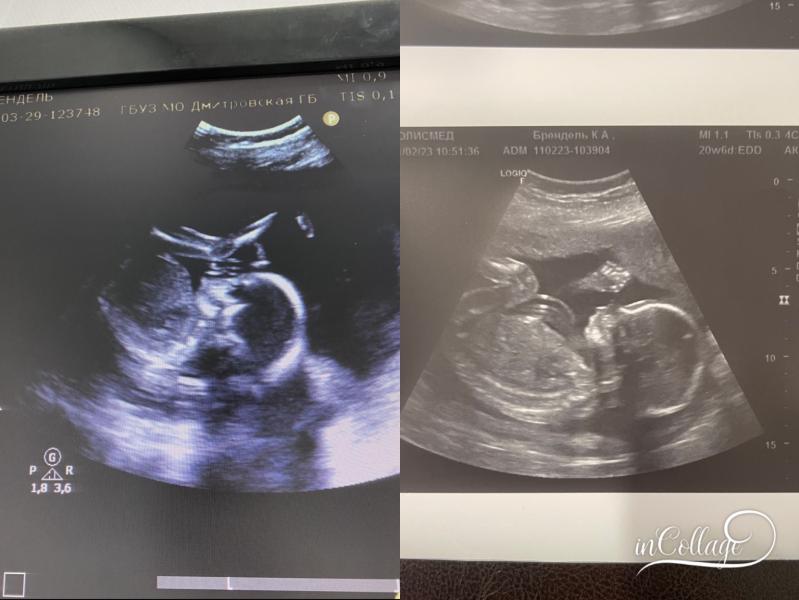

На первой фотке дочка💜, на второй сынок💙

Второй скрининг с дочкой ходила в 20.2 вес 313 гр

Сынок 20.6 вес 385🤯что за богатырь там внутри сидит, аж страшно😁

Такой сладкий малыш в животике сидит невозможно🥰 ❤️🌸очень похожи с сестренкой